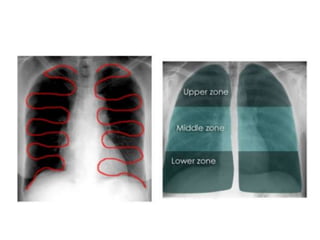

This document provides an overview of interpreting chest x-rays and identifies several key factors. It discusses the importance of inspiration, penetration, and rotation in obtaining a technically quality radiograph. It also outlines different views of chest x-rays including PA, AP, and lateral views. Finally, it identifies several anatomical structures that should be evaluated when interpreting a chest x-ray such as the lungs, heart, diaphragm, bones, and soft tissues.